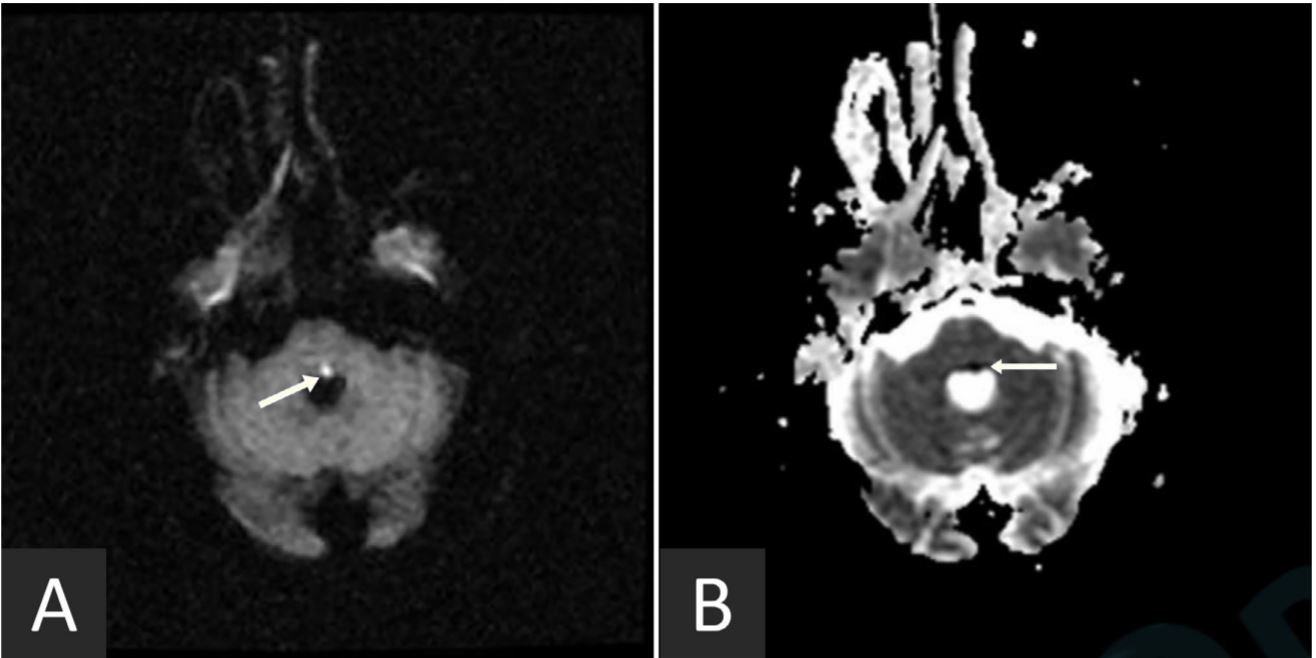

Trigeminal Nucleus Mri